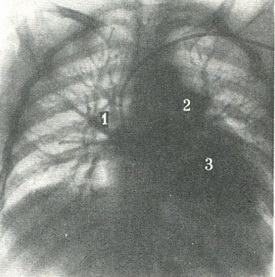

На прямій ангиограмме a. pulmonalis має довжину 3 см, діаметр 2 - 3 см і накладається на тінь хребта на рівні VI грудного хребця. Тут вона поділяється на праву і ліву гілки. Потім можна диференціювати всі сегментарні артерії. Вени верхньої і середньої часток з'єднуються в верхню легеневу вену, має косе положення, а вени нижньої частки - в нижню легеневу вену, розташовану горизонтально по відношенню до серця (рис. 314, 315).

![]() 315. Венозна фаза при загальній ангиопульмонографии (по Л. Д. Линденбратену). Введений Катетер у праве передсердя. Контрастированы легеневі вени (1), ліве передсердя (2), лівий шлуночок (3). Контрастна речовина досягло висхідної аорти.  |